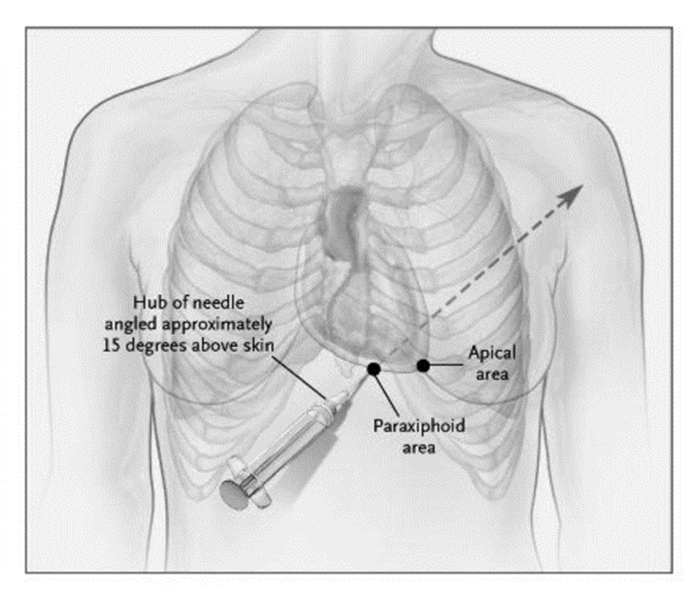

(3)超声引导下心包穿刺术(ultrasound for pericardiocentesis) 心脏压塞是临床常见的危重症之一,多继发外伤或心脏术后、急性心包炎症、恶性肿瘤等基础疾病,需积极的穿刺引流。精准的床旁超声定位下穿刺,对急诊引流心包积液,起着必不可少的作用[50, 51]。临床上床旁心超选择穿刺路径多为剑突下或心尖区途径(图 43)。剑突下途径是在剑突下与左肋弓下缘之间,朝向左肩方向,与皮肤呈15°~30°角将穿刺针刺入心包腔内。心尖区穿刺位点是在左乳头外侧肋间隙,心尖搏动最明显处。具体路径须根据操作者的习惯、手法和心包积液的分布来综合考虑。床旁超声与胸部CT等其他影像学检查相互印证,对于穿刺困难者合理选择体位和穿刺路径尤为重要。

|

| 图 43 床旁心超定位剑突下、心尖部位穿刺示意图 |